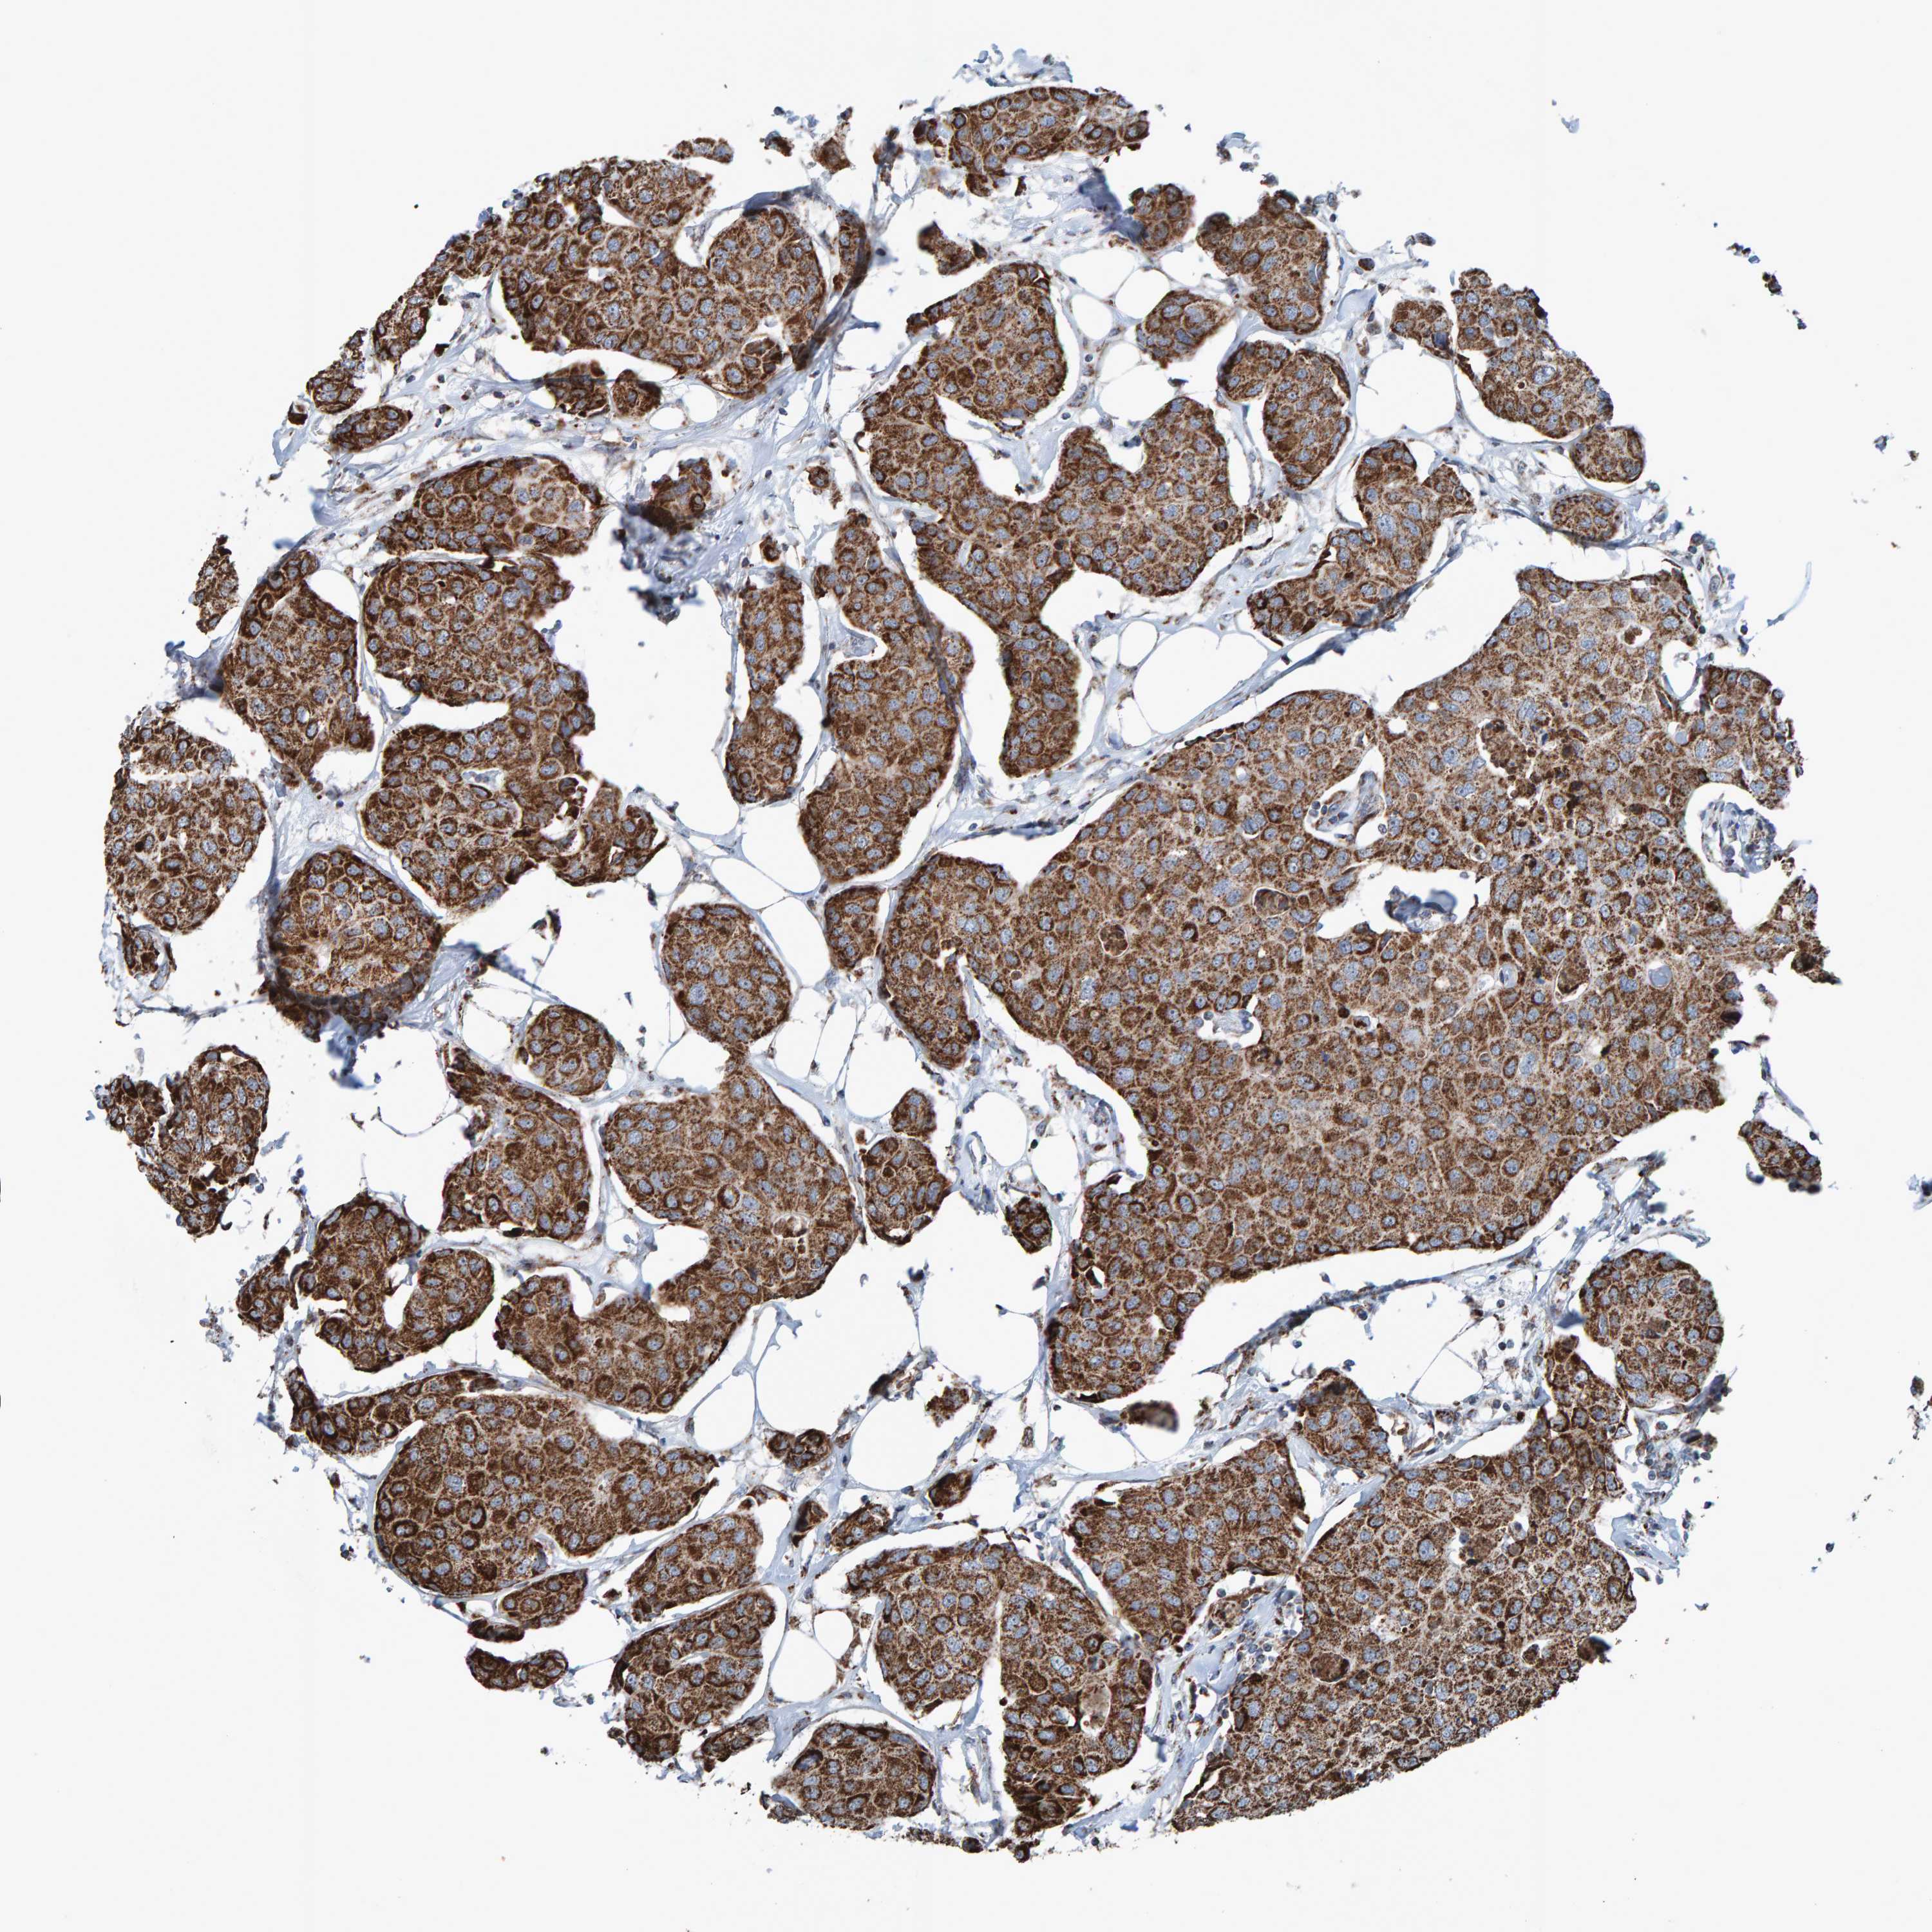

CANCER BREAST CANCER Show tissue menu

BRCA TCGA BRCA VALIDATION PROTEIN EXPRESSION

Breast cancer

Human cancer